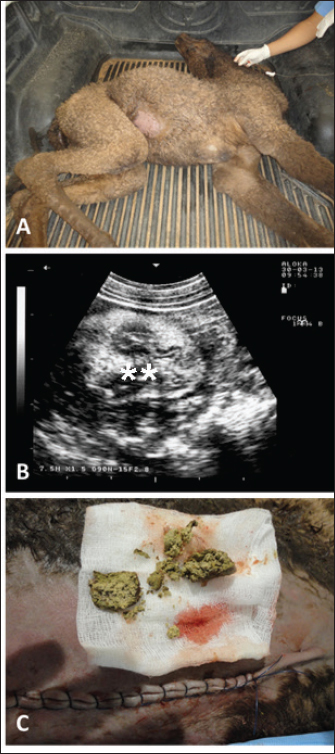

Full details including presenting complaints, symptoms, diagnosis, treatment, and outcome of the 25 dromedary camels with depraved appetites are listed in Table 1. The dromedary camels with depraved appetites had different presentations, but all of the examined animals had a history of eating foreign or inanimate objects. Pica was evident in some cases upon initial clinical examination (Fig. 1). Twelve of the camels (48%) were admitted with a history of loss of body weight and 8 (32%) with partial or complete loss of defection. Seven out of the nine (77.8%) lactating camels in this study suffered from decreased milk production. An example of such a case is shown in Figure 2. In animals undergoing laparotomy, the foreign bodies were surgically removed as shown in Figure 3. Bouts of repeated vomiting were also found in 5 (20%) of the camels. In animals that underwent rumenotomy, the foreign bodies were removed as in Figure 4. Eating feces (coprophagia) was also found in six camels as shown in Figure 5. Sixteen (64%) of the camels were recovered while the remaining 9 (36%) did not survive.

Sonographic and postmortem findings are summarized in Table 2. In cases of camels presented with a history of pica and with decreased or total absence of feces, the obstructing foreign body was imaged in 10 of the 25 camels (40%) occluding completely or partially the intestines that may be confirmed at abdominal surgery (Figs. 2, 3, and 6). Foreign bodies within the rumen could not be visualized with ultrasound owing to the gas content. In cases where the rumen is impacted by sand, small pin-points revealing acoustic enhancement were imaged in 5 (20%) of the camels. An example of these cases is shown in Figure 7. Foreign bodies were removed from the rumen or intestines at exploratory rumenotomy and laparotomy, which included plastics, cloths, sand, mud, robes, wool balls, glasses, or even metallic objects that were blunt or sharp (Figs. 8 and 9).

Fig. 3. Ultrasonographic findings in a 30-day camel calf with a history of pica. The calf was admitted with a 5-day history of no defection and abdominal distension (A). Image (B) shows an obstructing enterolith occluding the small intestines (stars) using a 7.5 MHz sector transducer. Image (C) shows the obstructing enterolith detected at right-sided surgical laparotomy.